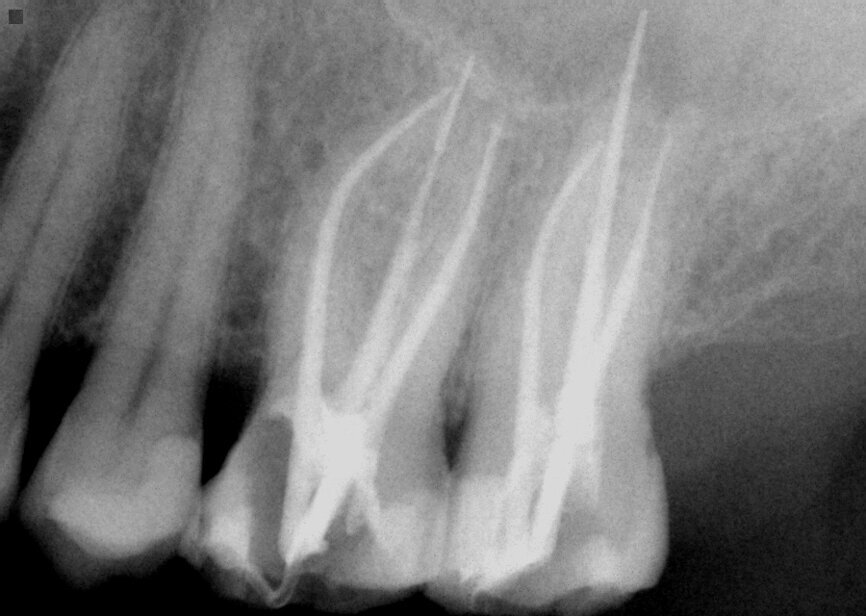

Fig. 15: Instrumentation performed with ExactTaperH DC files and obturation with a single cone of GP and Bioceramic Root Canal sealer completing endodontic treatment.

The teeth were isolated, and access performed with canal orifice identification. The SX file (ExactTaperH DC) was utilized to enlarge the canal orifice and aid in further file instrumentation. The canals were then instrumented to working length with the GP file. Each canal was instrumented with ExactTaperH DC files starting with the S1, then followed by the F1, F2 and F3 in the mesial-buccal and distal-buccal canals in both molars. The palatal canals in both teeth were competed with the F4 file. The canals were irrigated by alternating between sodium hypochlorite 3 percent (Vista Apex) and 17 percent EDTA solution (Vista Apex) during instrumentation and at completion. Canals were dried with paper points (ExactTaperH DC) matching the size of the final file used. Bioceramic Root Canal sealer (SS White) was mixed and dispensed on a pad. A gutta-percha cone (ExactTaperH DC) matching the final file size for each canal was coated with sealer and each canal was obturated in a single cone technique. The excess cones were cut off at the canal orifice and obturation was completed (Fig. 15). A temporary restoration was placed into both teeth using the GC Fuji Automix LC, and the patient was appointed to restore the two teeth.